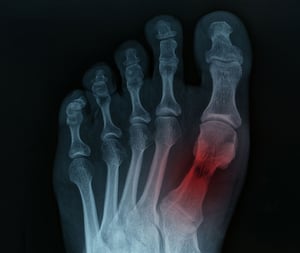

Age-related wear and tear, previous injuries, or inflammatory conditions cause arthritis in the foot and ankle joints, leading to pain, stiffness, and reduced mobility. Osteoarthritis commonly affects the big toe joint and ankle, causing morning stiffness and pain that worsens throughout the day. Post-traumatic arthritis can develop years after an ankle injury, even when the initial injury seemed to heal completely.